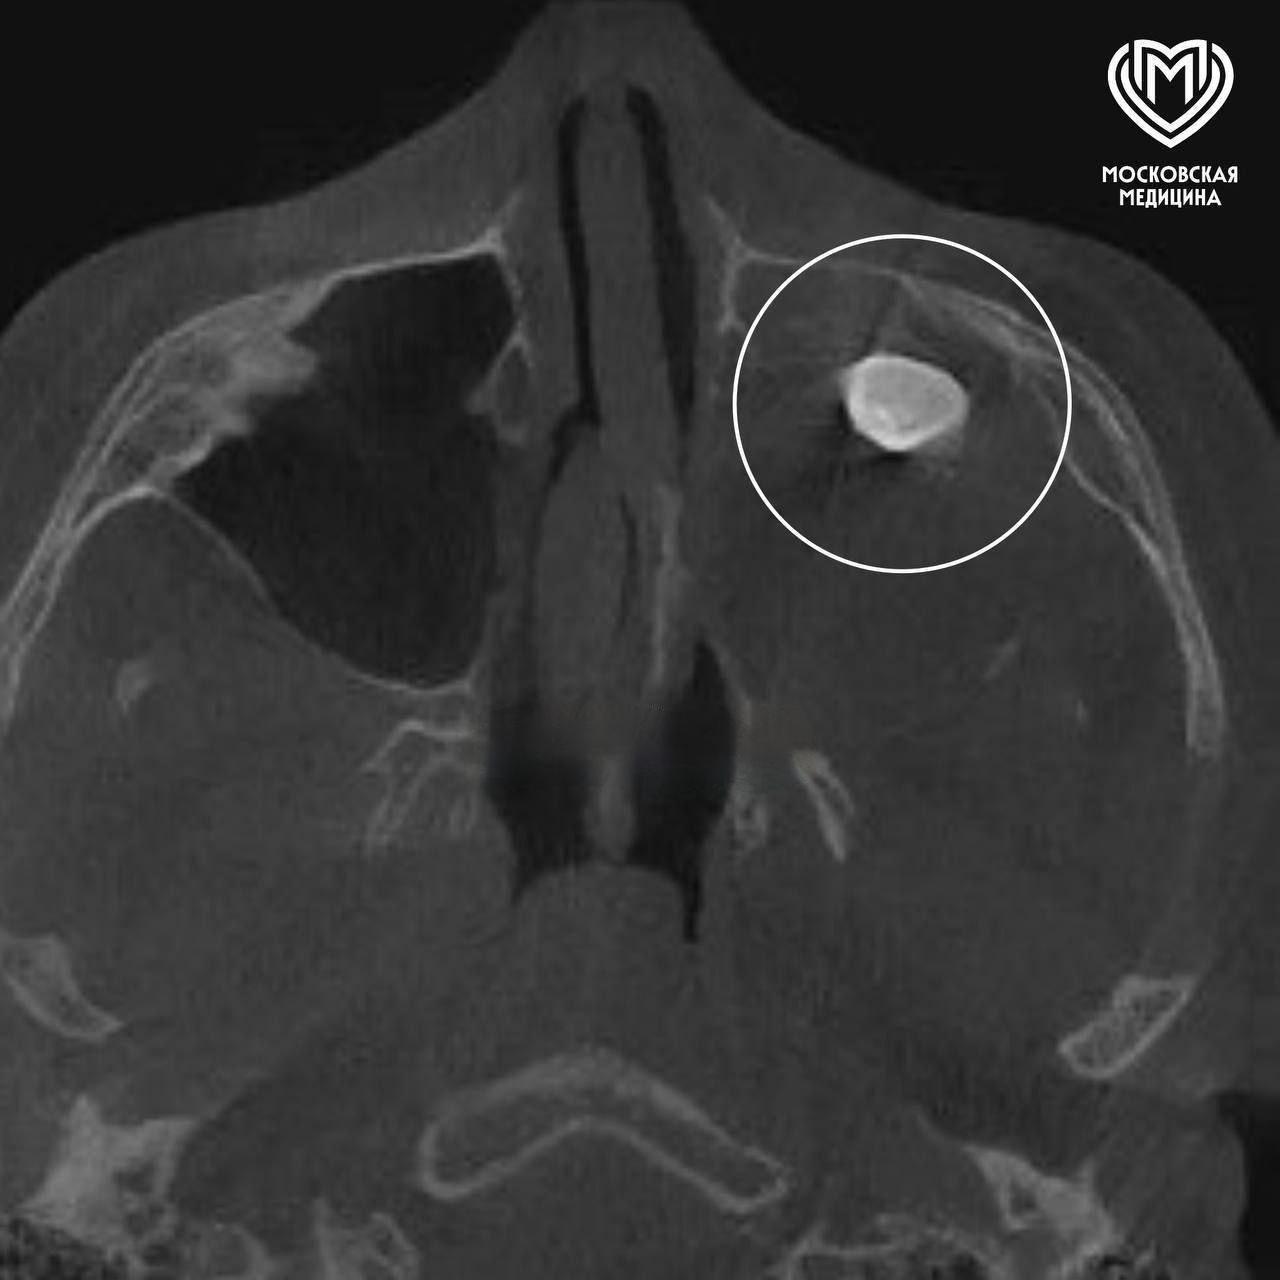

В Москве произошёл уникальный медицинский случай, который заставляет задуматься о возможностях и причудах человеческого организма. У 15-летнего подростка в носу обнаружили зуб. Да, именно так — настоящий зуб, который вырос не там, где ему положено. Подросток жаловался на постоянную заложенность носа и заметную асимметрию лица, что в итоге привело его к врачам.

После обследования выяснилось, что в гайморовой пазухе — это полость в верхней челюсти — находился зуб. Хирурги провели операцию по его удалению, и теперь парень дышит свободно, а его лицо вернулось к нормальной симметрии. Этот случай не только удивителен, но и демонстрирует, насколько сложным и иногда непредсказуемым может быть наше тело.